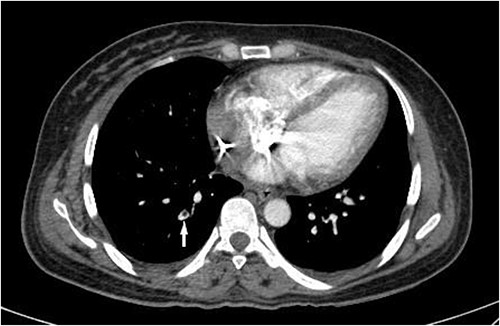

Although PRs decreased gradually after the second operation, they increased again after 24 h. This was accompanied by a body temperature rise to 38.7°C. A CT pulmonary angiography (CTPA) was performed following the fever work-up, revealing lobar, segmental and subsegmental filling defects in the posterior branches of the right pulmonary artery (Fig. 2). After confirming the diagnosis of PE, the patient received anticoagulation therapy with caution. Ultimately, without experiencing further complications, the patient survived and was discharged after 3 weeks in stable condition and partial recovery.

CT pulmonary angiogram on the third day of hospital admission shows a filling defect in a subsegmental branch of the right posterior pulmonary artery (white arrow), compatible with a PE.